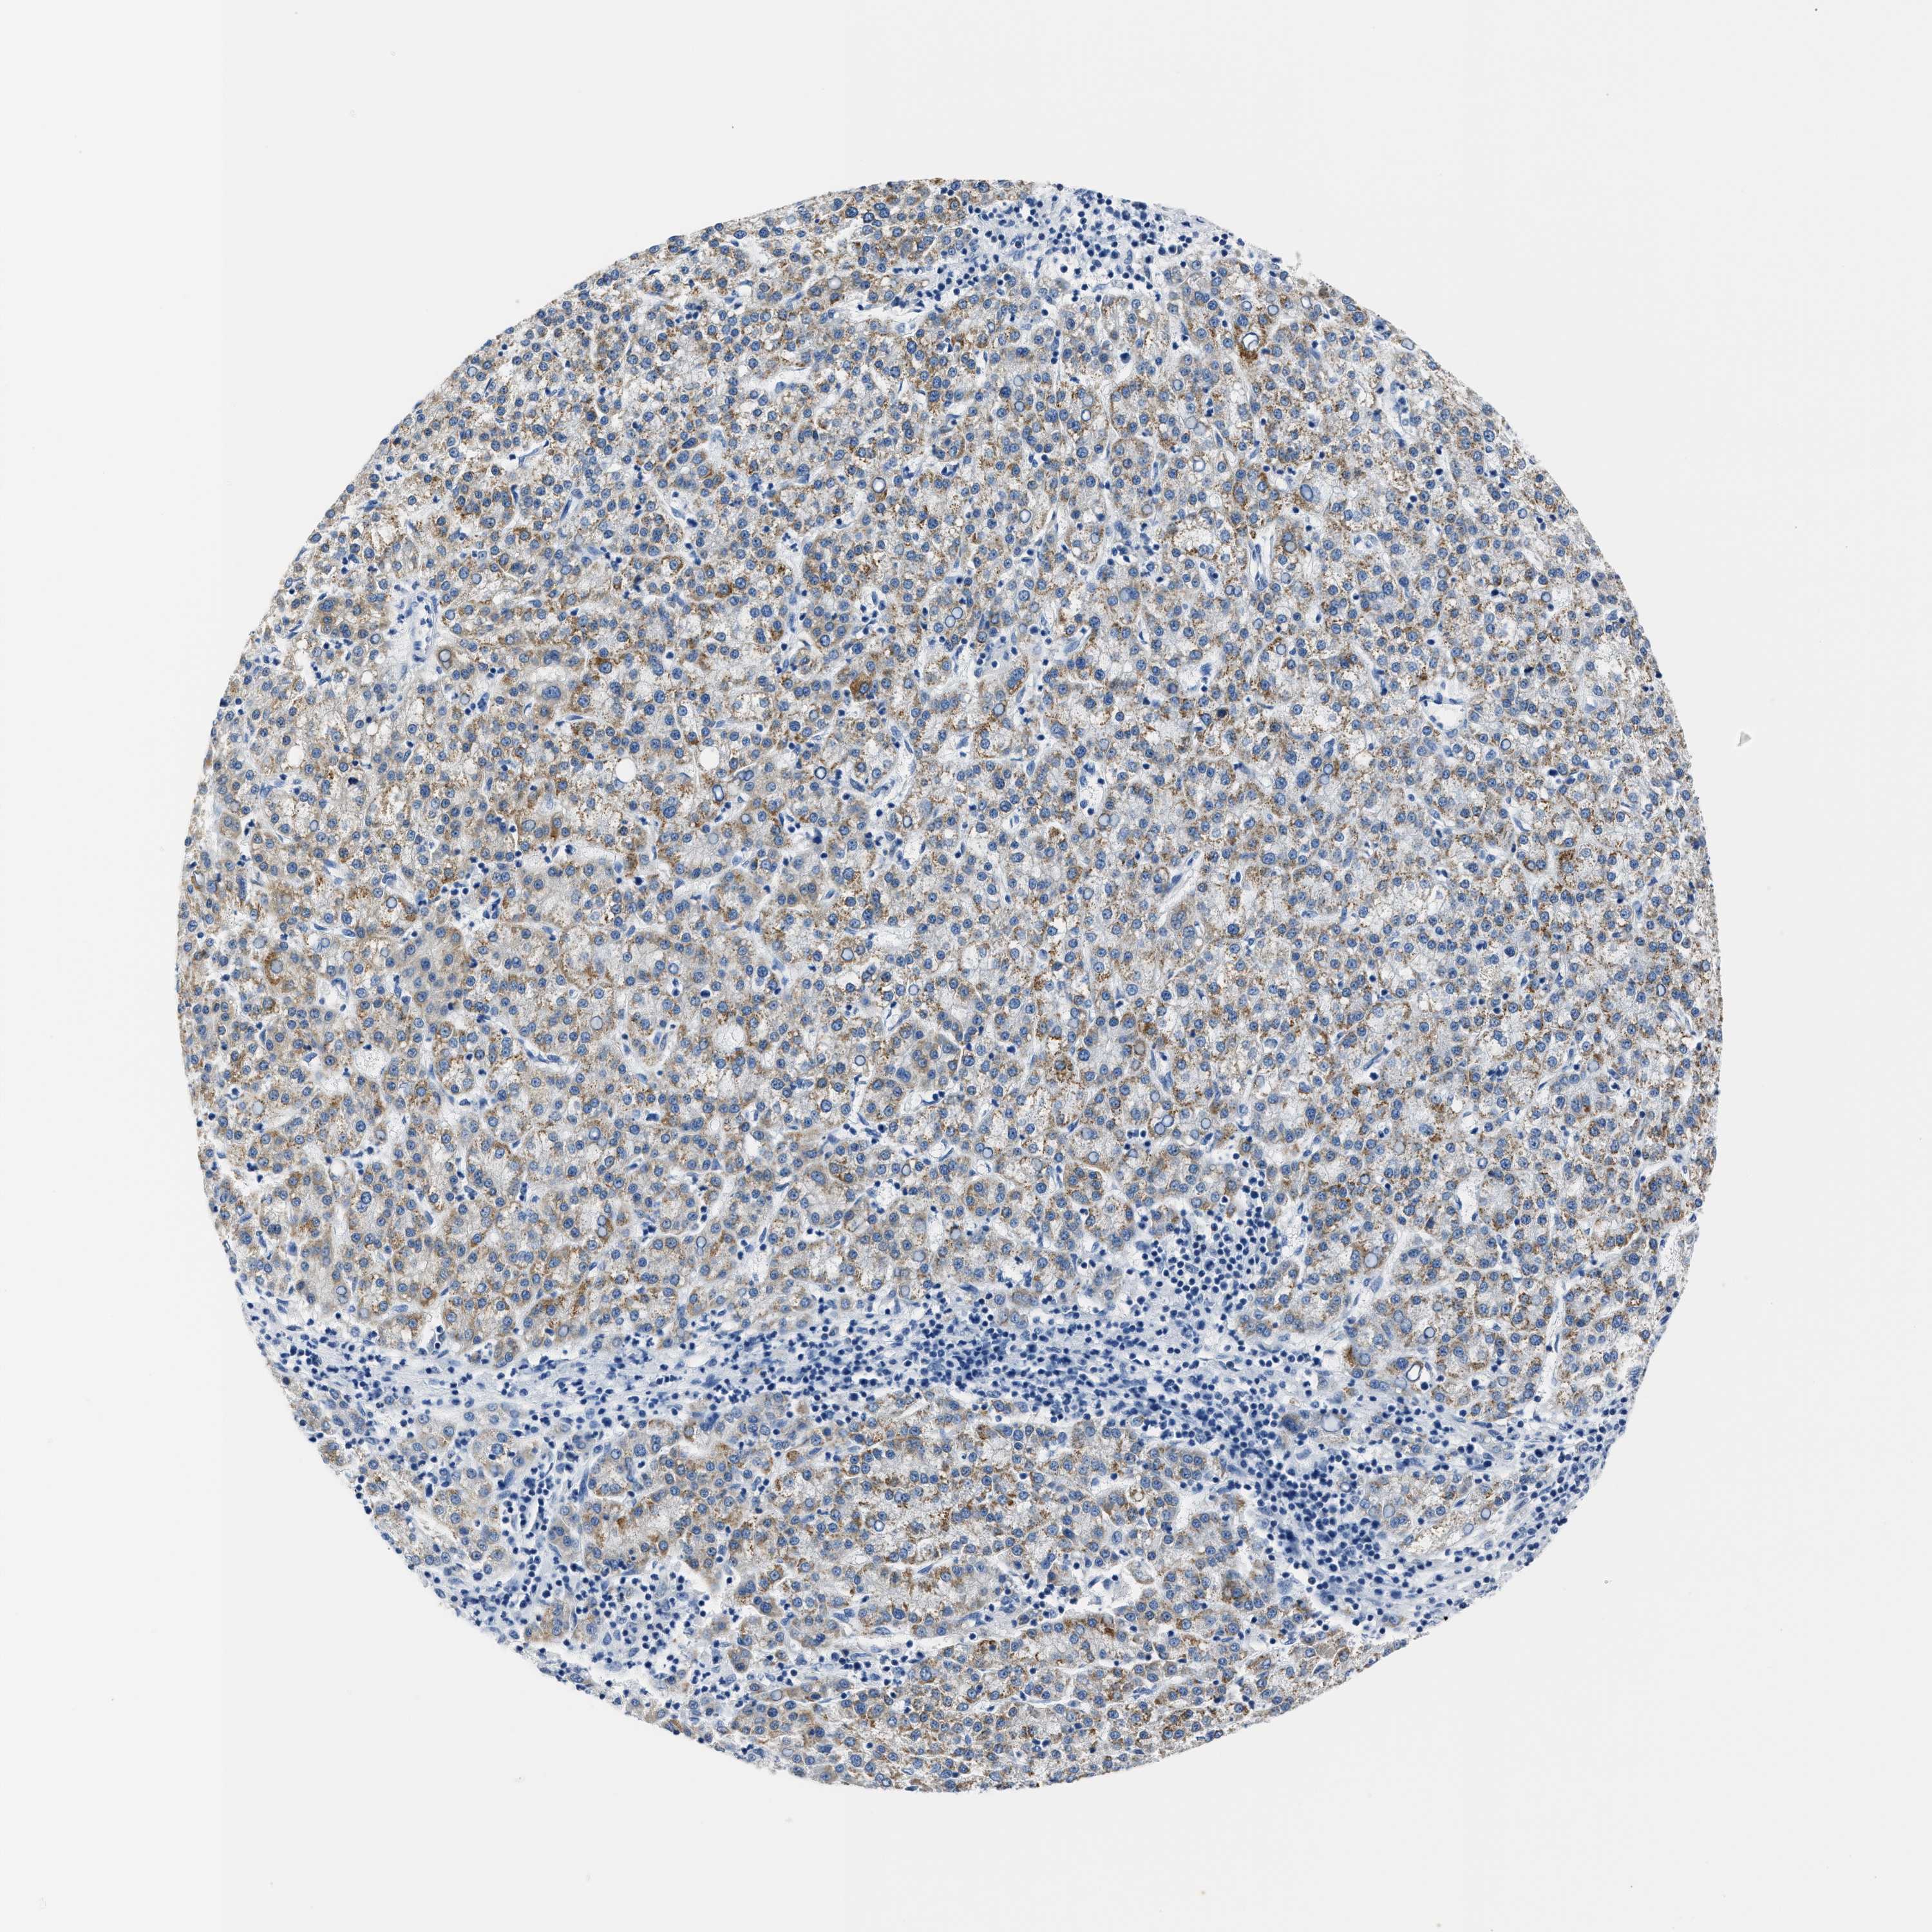

LIVER CANCER - Protein expressioni

A mouse-over function shows sample information and annotation data. Click on an image to view it in a full screen mode. Samples can be filtered based on level of antibody staining by selecting one or several of the following categories: high, medium, low and not detected. The assay and annotation is described here.

Note that samples used for immunohistochemistry by the Human Protein Atlas do not correspond to samples in the TCGA dataset.

Antibody stainingi

Antibody staining in the annotated cell types in the current human tissue is reported as not detected, low, medium, or high, based on conventional immunohistochemistry profiling in selected tissues. This score is based on the combination of the staining intensity and fraction of stained cells.

Each image is clickable and will lead to virtual microscopy that enables deeper exploration of all samples and also displays staining intensity scores, fraction scores and subcellular localization as well as patient and tissue information for each sample.

Antibody HPA019527

Antibody HPA020912

Antibody CAB001809

Staining

High

Medium

Low

Not detected

Intensity

Strong

Moderate

Weak

Negative

Quantity

>75%

75%-25%

<25%

None

Location

Nuclear

Cytoplasmic/membranous

Cytoplasmic/membranous,nuclear

Cholangiocarcinoma

Carcinoma, Hepatocellular, NOS